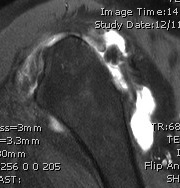

MRI

Rotator cuff tears

MRI with supraspinatus tear, Hill Sachs lesion and significant glenoid bony deficiency